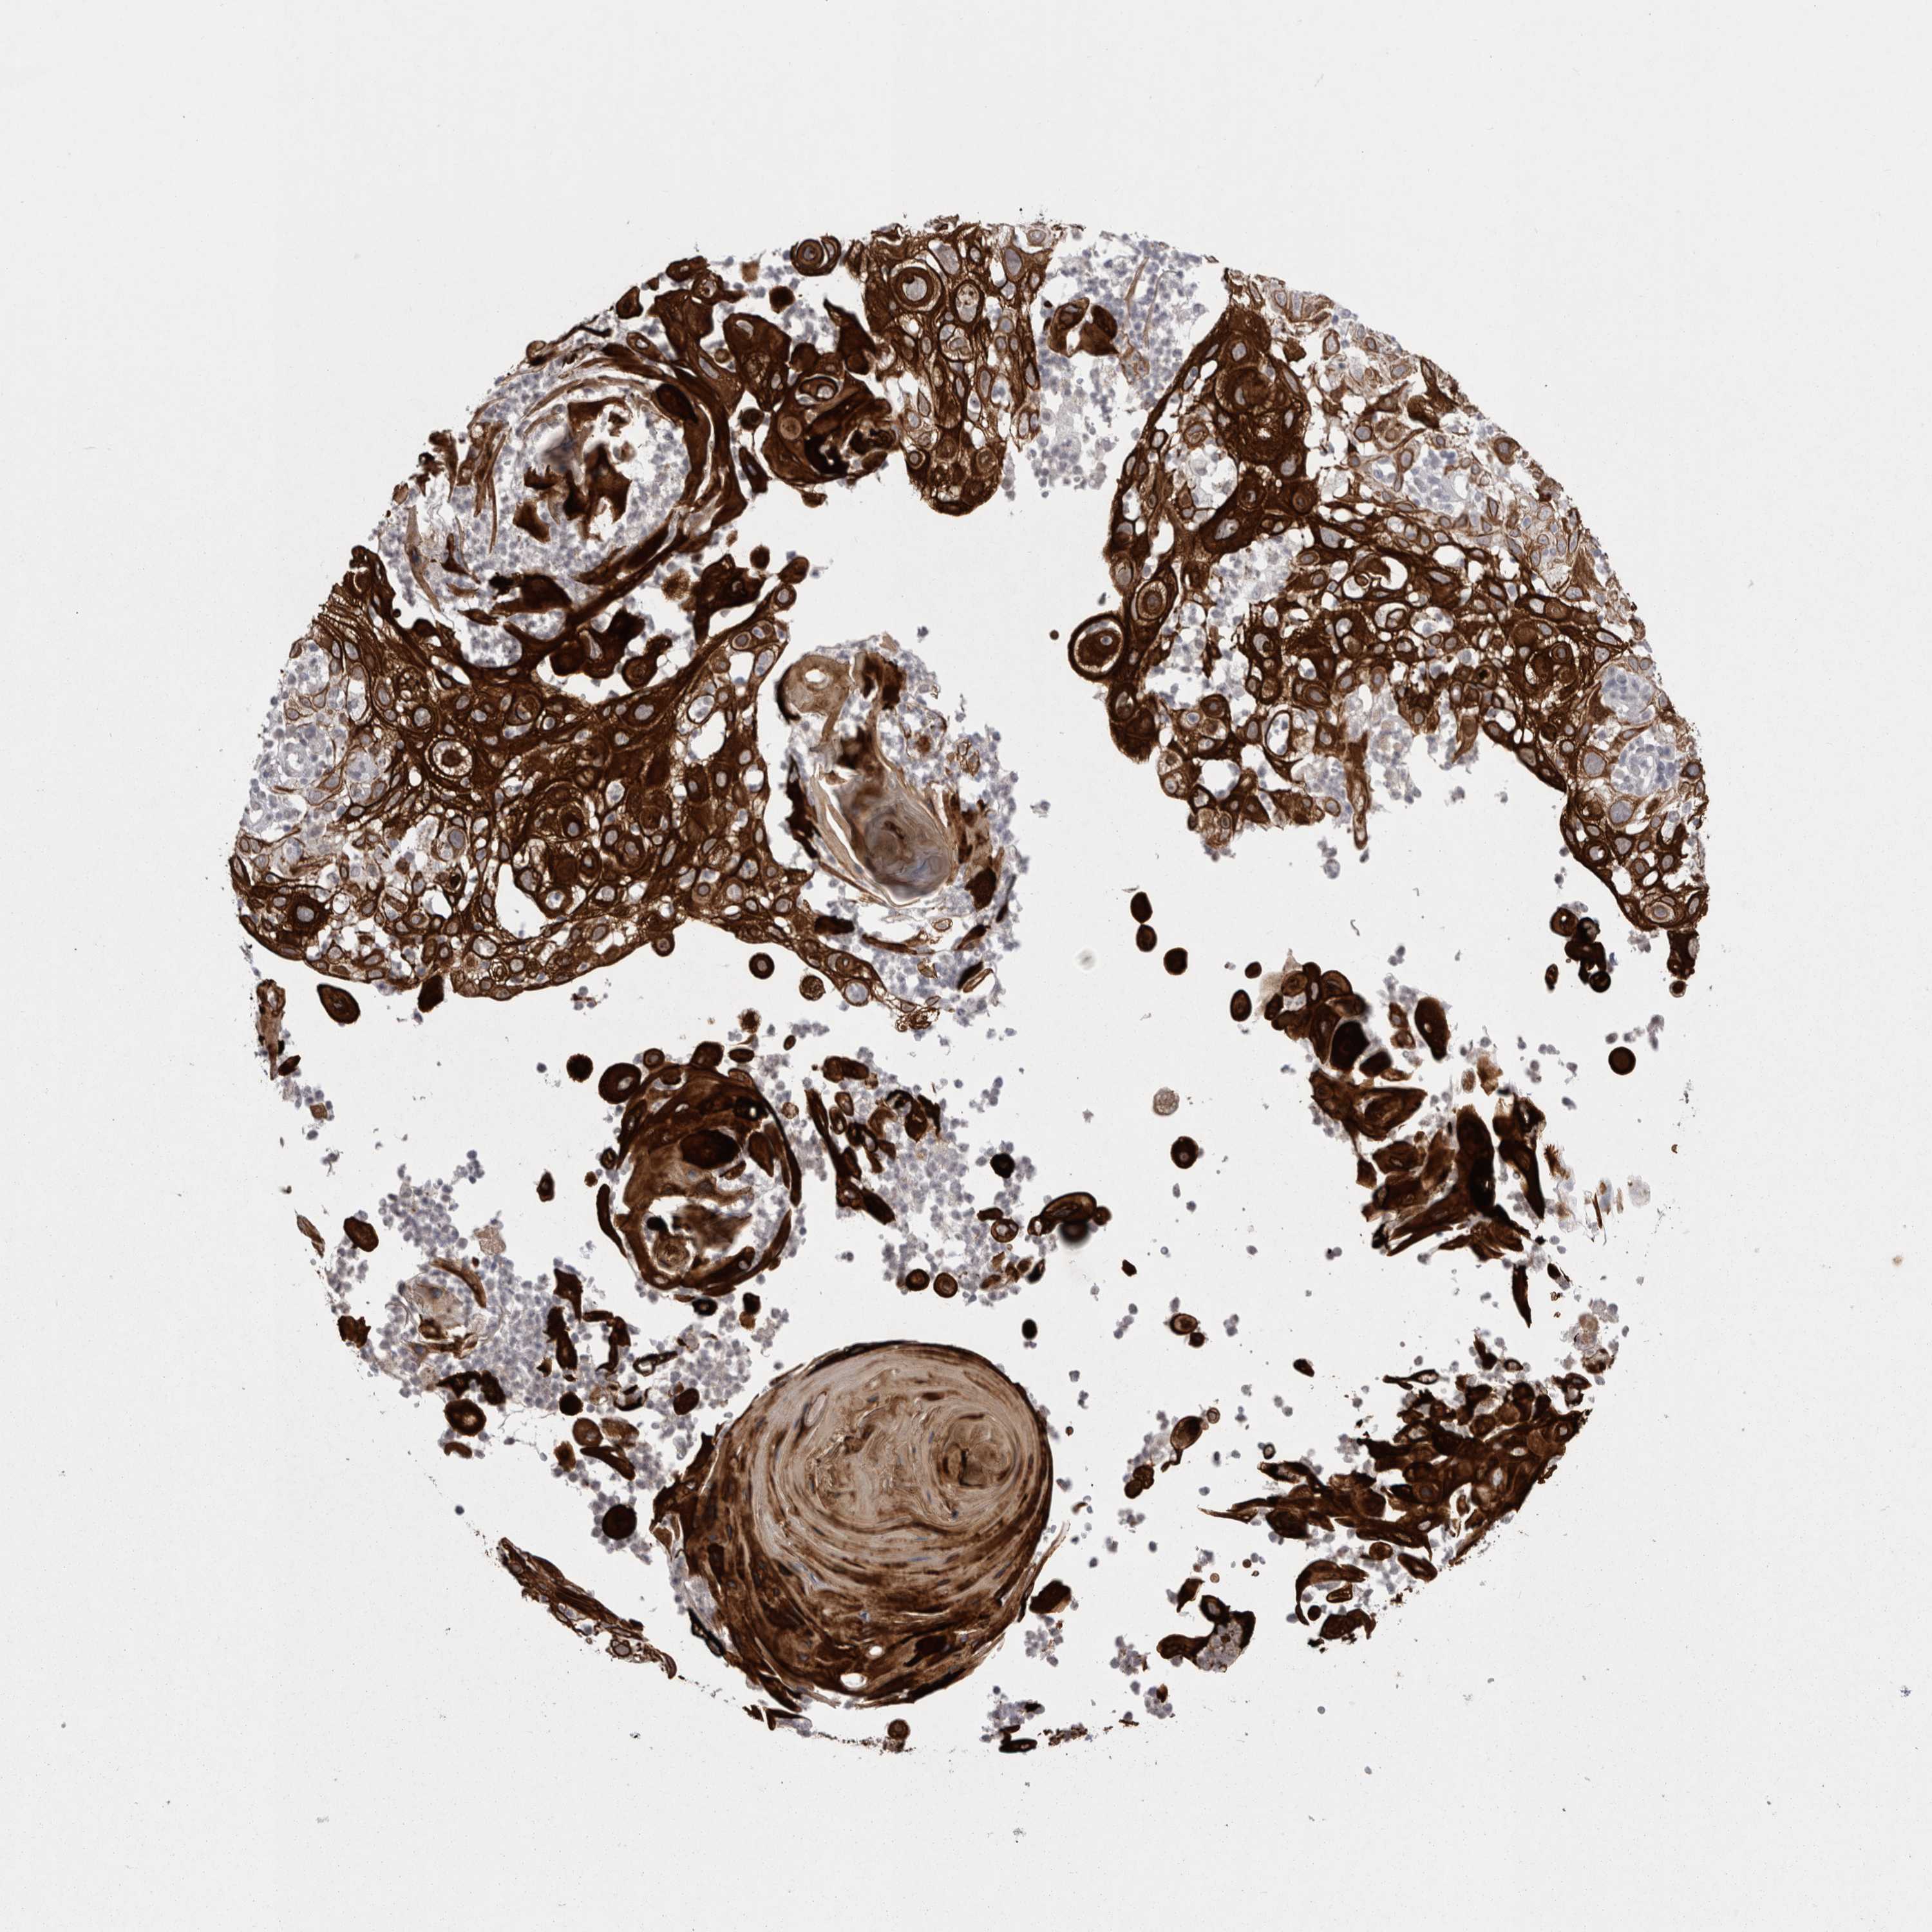

SKIN CANCER - Protein expressioni

A mouse-over function shows sample information and annotation data. Click on an image to view it in a full screen mode. Samples can be filtered based on level of antibody staining by selecting one or several of the following categories: high, medium, low and not detected. The assay and annotation is described here.

Antibody stainingi

Antibody staining in the annotated cell types in the current human tissue is reported as not detected, low, medium, or high, based on conventional immunohistochemistry profiling in selected tissues. This score is based on the combination of the staining intensity and fraction of stained cells.

Each image is clickable and will lead to virtual microscopy that enables deeper exploration of all samples and also displays staining intensity scores, fraction scores and subcellular localization as well as patient and tissue information for each sample.

Antibody HPA037764

Squamous cell carcinoma, NOS